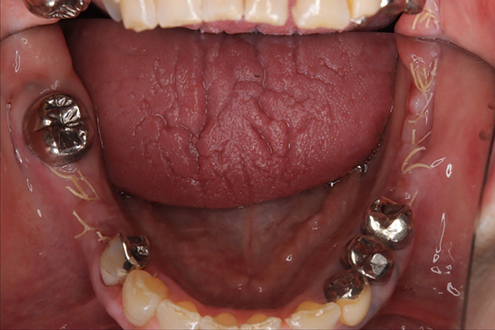

| 治療部位 | 両側下顎臼歯部 |

|---|---|

| インプラント本数 | 1本ずつ |

| 単価 | 40万円/本 |

| 合計費用 | 40万円 |